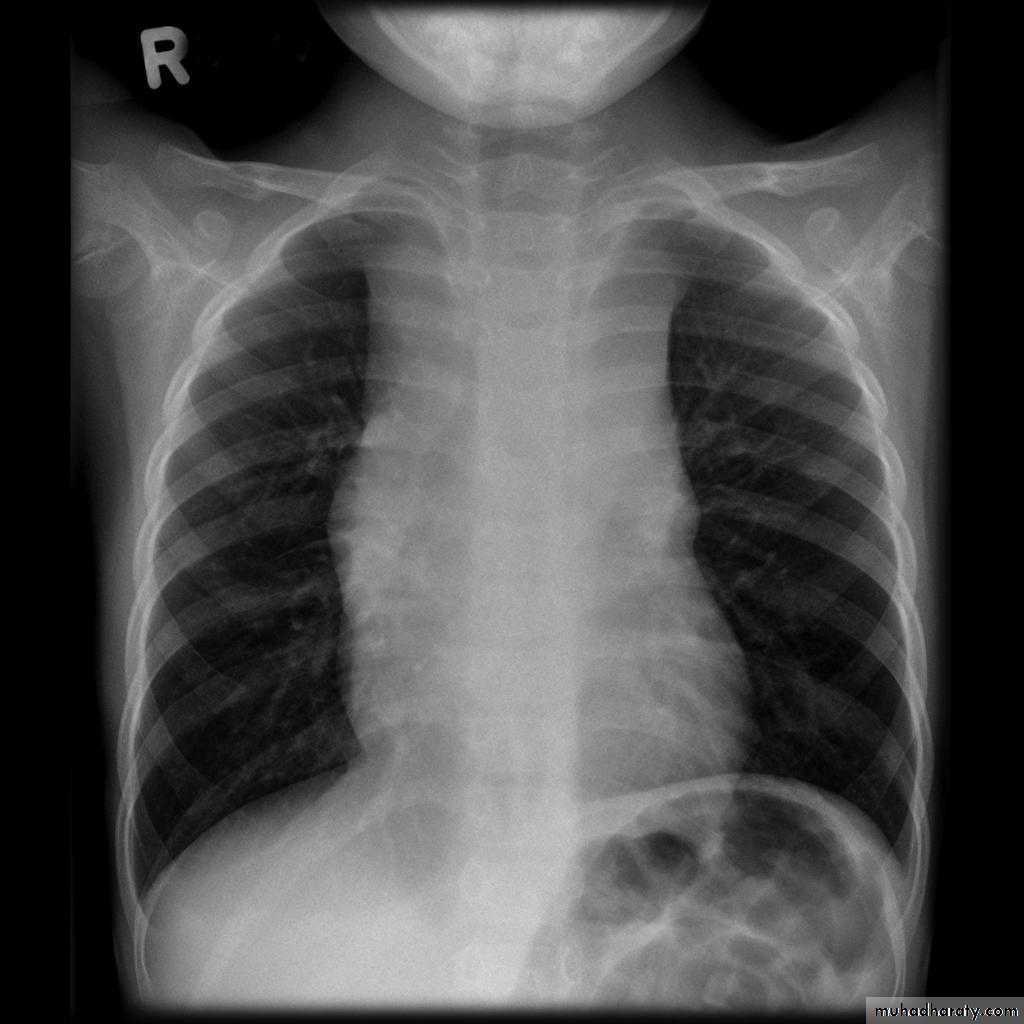

Plain films may classically show :

1. "boot shaped" heart with an upturned cardiac apex due to right ventricular hypertrophy and concave pulmonary arterial segment.

2.Pulmonary oligaemia due to decreased pulmonary arterial flow.

3.Right sided aortic arch is seen in 25%.

"boot shaped" heart ( TOF )

TOF